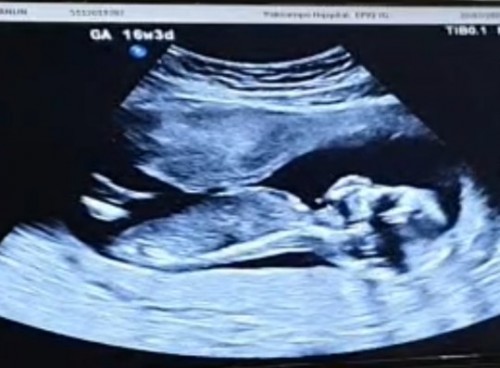

กี่วีคแล้วคะ